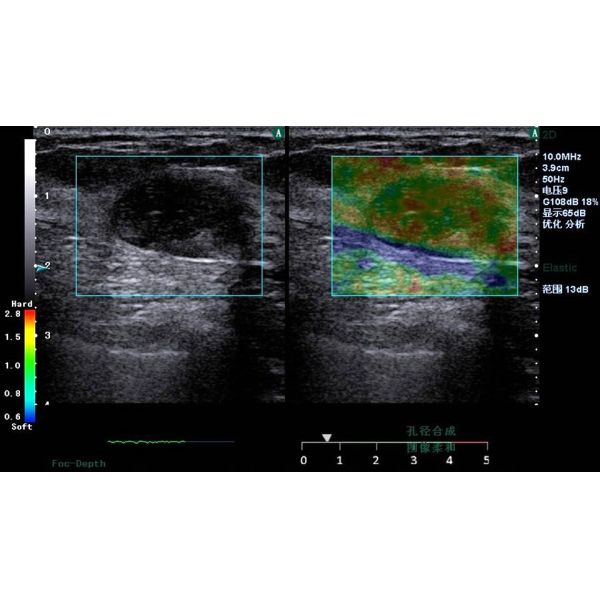

Elasticity Imaging in Healthcare

1. Introduction

Tissue elasticity offers clinically significant information on

tumor and lesion growth, including early state characterization

that may greatly assist early diagnosis. We present

visualization of tissue elasticity through two methods:

1) Freehand elastography using manual probe compression

2) Sound-Push© elastography & shear wave speed

estimation using ARFI

Figure 3. Clinical strain images of confirmed (a) inflammation lesion; (b) benign and (c) malignant breast tumor

2. Freehand elastography

Motion tracking of manual compression or breathing

induced movement generates a strain image

representing the elasticity of the underlying tissue. Statemed